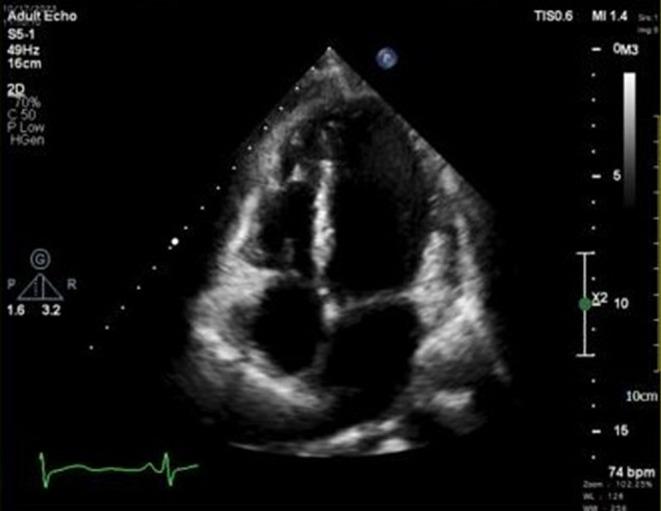

Cardiac papillary fibroelastomas (CPF) are rare, benign tumors with thromboembolic potential. We present a 40-year-old male with a right atrial CPF, referred with acute chest pain. Advanced imaging and surgical excision with tricuspid valve repair were crucial, emphasizing the need for early detection and intervention in symptomatic and asymptomatic cases.

心脏乳头状纤维弹性瘤(CPF)是一种罕见的具有血栓栓塞潜在风险的良性肿瘤。我们报告一名40岁男性患有右心房CPF,因急性胸痛前来就诊。先进的影像学检查以及联合三尖瓣修复的手术切除至关重要,这凸显了对有症状和无症状病例进行早期检测和干预的必要性。